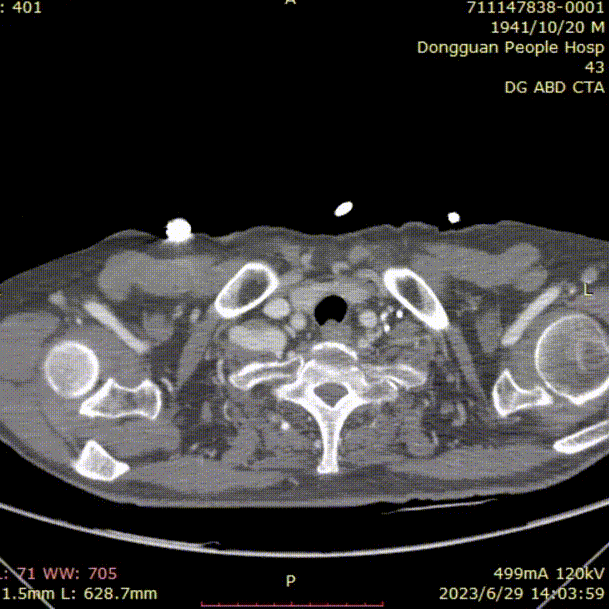

专科及辅助检查:全主动脉CTA:自胸降主动脉起始至腹主动脉段夹层形成,左侧髂总、髂外动脉闭塞。

横断面影像

1)内膜多处撕裂,真腔严重狭窄。

2)CA假腔供血,SMA双腔供血,LRA假腔供血,RRA真腔供血,腹主段闭塞。